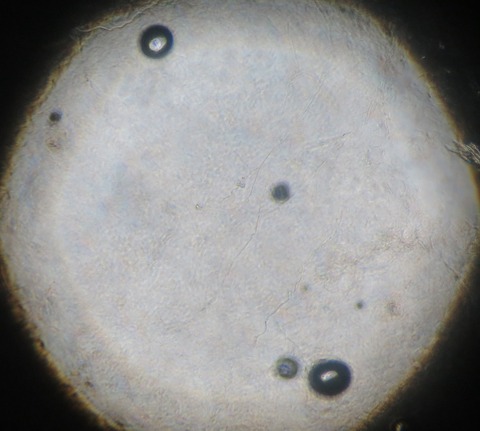

当院では、キャンデラ社のジェントル・マックス・プロによる医療レーザー脱毛を行っています。

アレキサンドライトレーザーとヤグレーザーを装備した最新型のレーザー機です。

肌色の濃い方、アレキサンドライトレーザーで残った体毛も照射可能です。